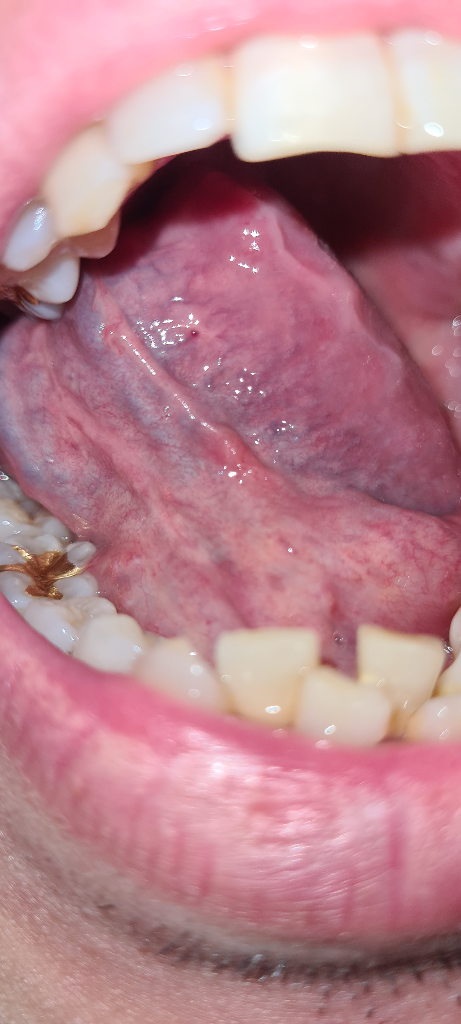

혀 아래 붉은 돌기?점이 있는데 뭘까요?

한 5주 전에 붉은 점 같은게 확인이 되었습니다. 통증은 없었는데 계속 5주가 넘어도 사라지지 않네요.

이번주에는 그 옆에 구내염 같은게 생기는지 약간 통증도 있고요.

일반 구내염은 아닌 것 같은데, 당장 한국 병원 방문은 어려워서 물어봅니다.

• 1번 째 사진

구강의 붉은 점에 대해 질문해 주셨는데요, 많이 걱정되셨을 것 같습니다. 답변해 드리겠습니다.

말씀하신 증상은 여러가지 원인에 의해서도 발생할 수 있습니다만, 일반적으로 증상이 2주 이상 지속되면 검사가 필요합니다. 증상이 5주 이상 지속되고 있다면, 검사가 필요한 상황으로 생각됩니다.

구강암의 증상 중 하나로 구강 내에 호전되지 않는 궤양이나 변색이 있는 경우, 지속적인 이물감이나 통증이 있을 수 있습니다. 증상의 양상을 잘 살펴보시고 이비인후과 또는 구강내과 진료를 보시는 것이 좋겠습니다.